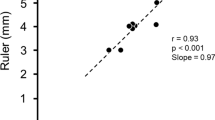

Accuracy

Accurate muscle thickness measurement depends not only on operator skills but also on technical aspects related to ultrasound physics and patient characteristics. Unclarity of surrounding membranes and insufficient ultrasound beam angulation to muscle axis may lead to measurement error. Furthermore, the spatial axial resolution (depth resolution, i.e., ½ spatial pulse length) of the probe plays a critical role. Given that the ultrasound pulse length is typically two cycles and that the ultrasound wavelength of a 10 MHz transducer is 0.15 mm (i.e., wavelength = speed of sound in soft tissue/frequency = 1540 m/s/10 MHz = 0.15 mm), the corresponding depth resolution is ½ (2 × 0.15) = 0.15 mm, which is in the same order as the intra-observer reproducibility and sufficient in order to visualize the diaphragm. Based on the ultrasound technique and equipment used, identification of the smallest detectable change that is permitted is fundamental to distinguish true changes in muscle thickness from artifact.